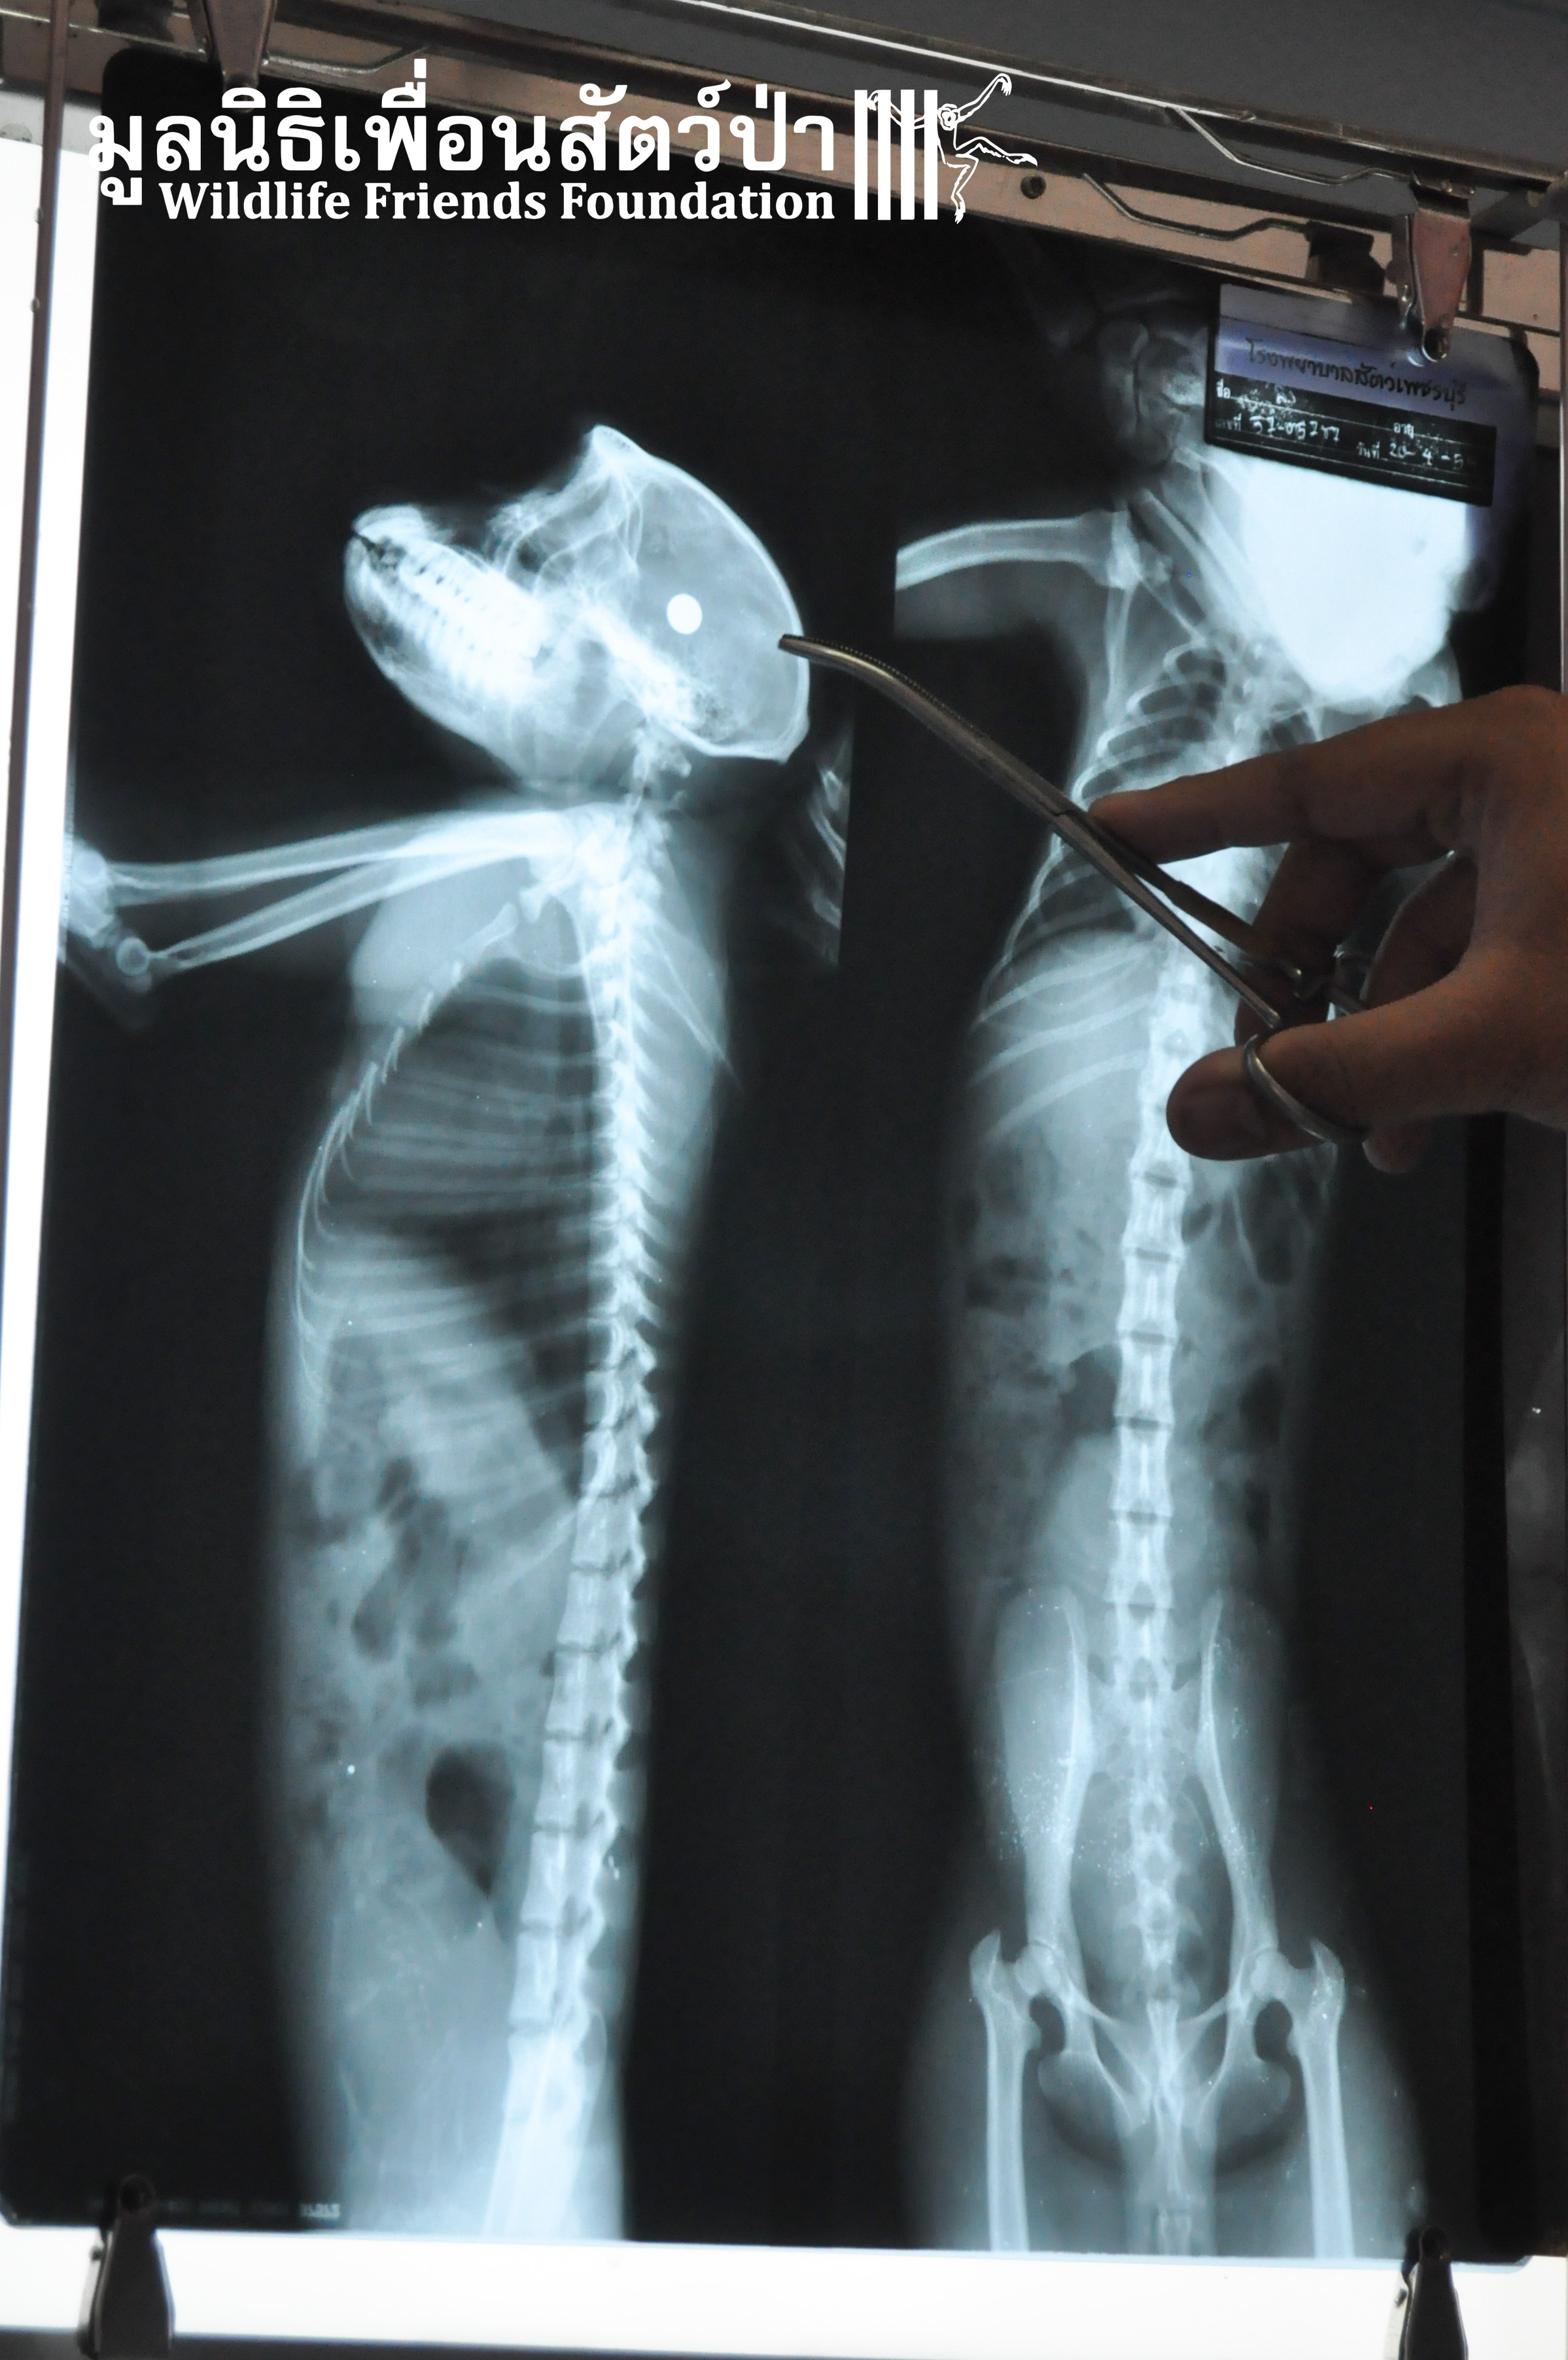

Yesterday we received a call from a concerned local man about a long-tailed macaque (Macaca fascicularis) that had been found by the side a busy road within a highly populated industrial area in Cha-am close to the WFFT Wildlife Rescue Centre. The compassionate local that found her thought she had been attacked by a pack of feral dogs. The WFFT Rescue Team set out immediately to help this poor soul, after the initial health check, the vet team found a puncture wound on the right side of her head, and it seemed that she had some kind of nervous damage to the right side of her body. She was rushed directly to an animal hospital nearby so an x-ray could be performed. After examining the results of the x-ray it was found that a bullet was lodged in her head, not only this, we found that she was carrying an unborn infant. This is a bleak reminder of the challenges faced by our team and Thailand’s urban macaques, those wild macaques that live in close proximity to human settlements.

Sadly, the brain damage caused by the soulless person who shot this monkey in the head was to much for her to overcome. Along with her unborn baby, she is no longer with us, she is now at peace and will never again have to overcome the challenges of surviving in this heavily overpopulated world.